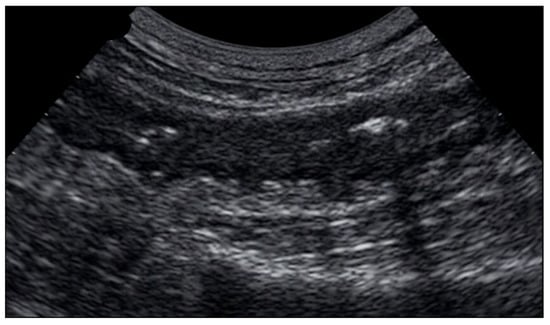

7. Gastrointestinal Perforation

8. Ischemic Bowel Disease

8.1. Non-Occlusive Mesenteric Ischemia